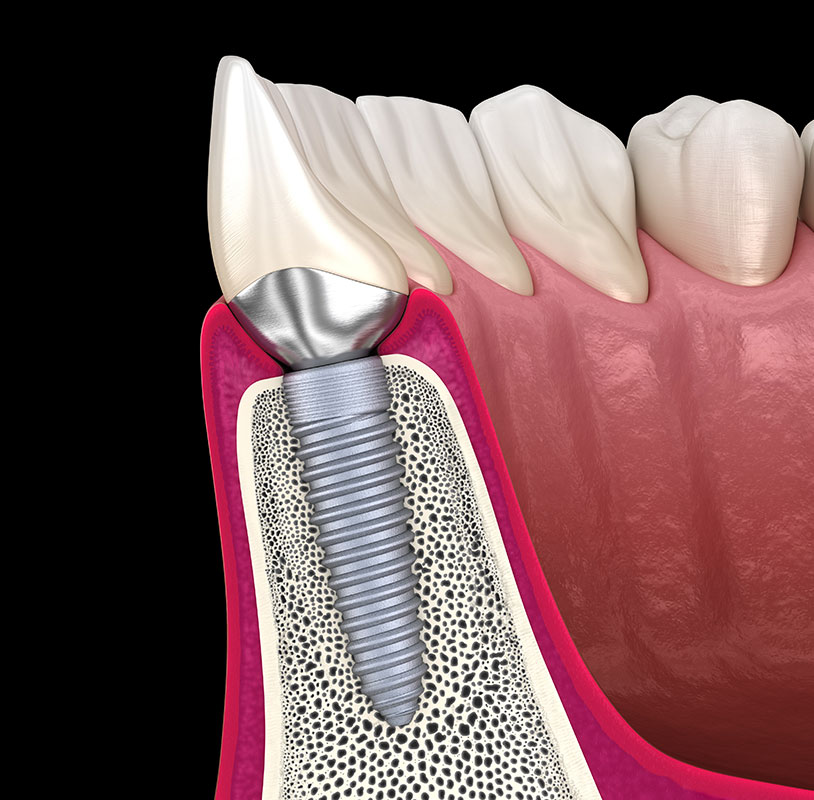

歯を失ってしまった場合、欠損部に人工歯根と人工歯を取り付け、機能性と審美性を回復させる治療です。豊富な治療経験と高い技術力をいかし、1本欠損から全部欠損まで、骨の少ない場合も含めて、要求の高い複雑なケースにも対応しています。痛みや腫れの少ない低侵襲インプラント治療のご提供を心がけています。

科学的根拠に基づいた的確な診査・診断と治療プラニング、高度な外科手技と合わせ、安全と信頼性に優れたインプラントシステムを導入し、高い成功率と満足を目指しています。